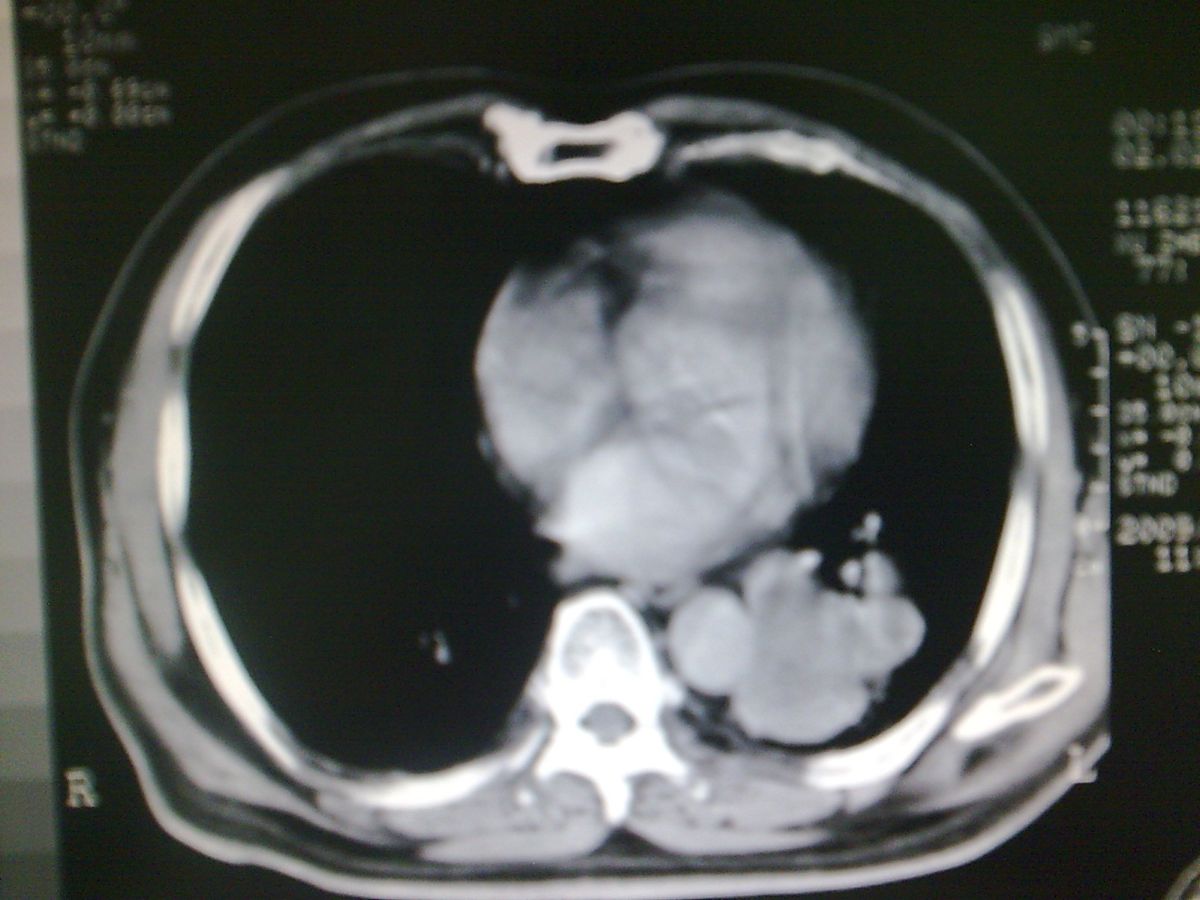

标题: CT19282:男性,70岁,咳血, [打印本页]

标题: CT19282:男性,70岁,咳血,

图片少了些,考虑周围性肺癌

考虑周围性肺癌

周围型肺癌。

考虑左下肺周围性肺癌。

考虑左肺下叶周围型肺癌可能。